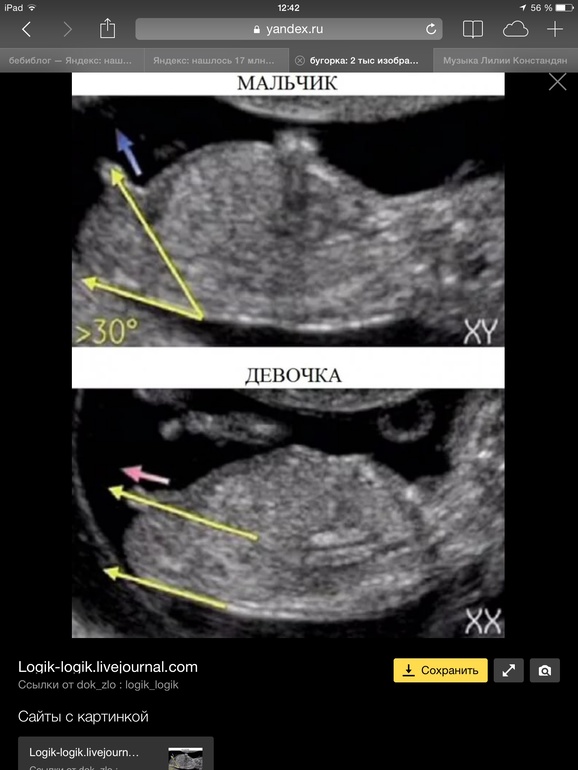

По наклону угорка на этом снимке я бы подумала что мальчик... но мало ли как там бывает) всё равно пока предположение... но правда мн5 с поллм не ошибались с первого узи в 12 недель...

На 12й неделе между ножек у всех одинаково, как у мальчиков, так и у девочек, определить можно только по углу наклона этой штучки, и то это будет только предположение пола, которое подтвердят или опровергнут на 2м скриниговом узи)

Определить можно ,как раз таки в нормальной литературе это указано)

Наклоны полового бугорка,если плод лежит хорошо ,узист опытный и хорошее оборудование ,то скажут с большой точностью,у нас узистка в городе в 12 недель с полом не ошибалась,и в 12,5 недель сказала что 100% девочка,так и было

На этом сроке пол можно определить только по наклону полового бугорка, который есть и у мальчиков и у девочек. Размер значения не имеет))